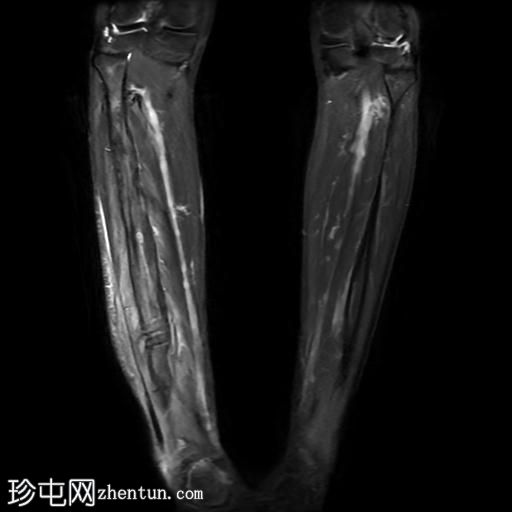

冠状位

STIR序列

腓骨可见广泛的骨髓水肿,伴有明显的皮质和骨膜增厚,整个腓骨均呈高信号。腓骨外侧中下三分之一交界处可见局灶性皮质破坏,并可见一条高信号瘘管延伸至周围皮肤。

此外,软组织(包括肌肉和皮下组织)也受累。

腓骨弥漫性骨髓信号异常,伴有明显的皮质和骨膜增厚,窦道自腓骨延伸至皮下区域。MRI 影像学表现符合腓骨骨髓炎。